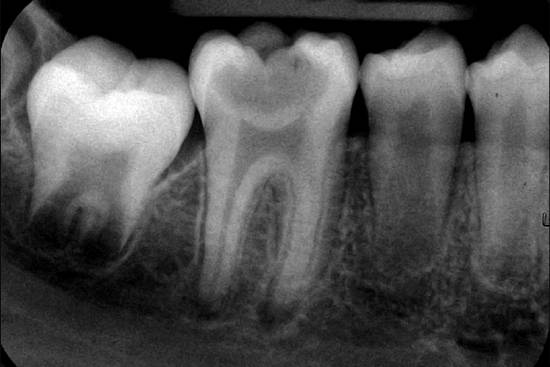

Фото и рентген

Чтобы с большей уверенностью можно было говорить о хроническом пульпите, необходимо знать, как он выглядит. Для этого мы предлагаем вам ознакомиться с фотографиями и рентгенограммами:

- Врач обследует поверхность проблемного зуба, но если установить пульпит визуально не удается, то пациента отправляют на рентгенограмму, часто используют и эод (электродиагностику).

Завершающим этапом лечения является пломбирование зубной полости. После установки пломбы следует проконтролировать состояние зуба путем рентгенограммы, при этом особое внимание обращают на качество пломбирования зубных каналов.